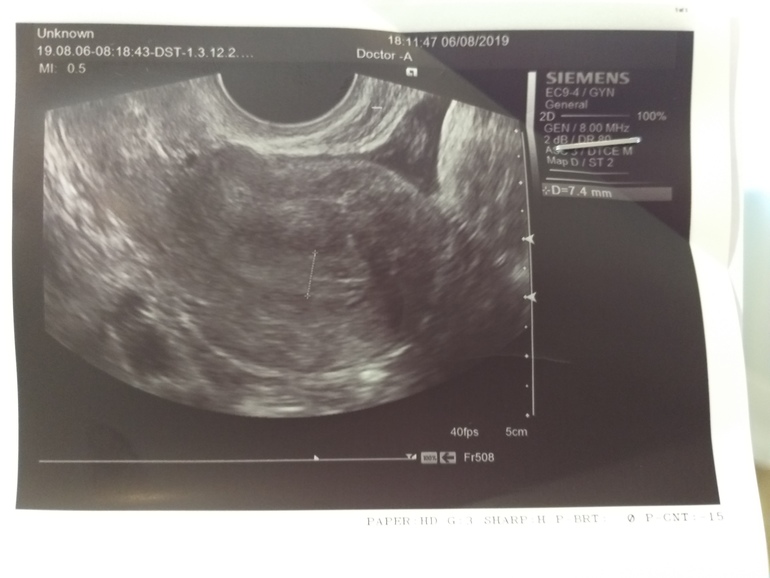

Плюс я так понимаю эндометрий очень тонкий для 18 ДЦ.

Посмотрите пожалуйста заключение, может у кого так было? Что в итоге оказалось? Наступала ли беременность при такой толщине эндометрия??